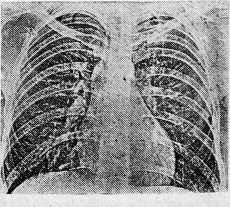

На пленочной рентгенограмме картина слева идентична с данными ЭРГ, справа тень на II ребре более отчетлива, усиление и деформация легочного рисунка выражены в меньшей степени, на фоне его обнаружены еще 6 округлых теней. Одна диаметром 1 см локализуется в среднем легочном поле и четыре диаметром 3 и 4 мм в нижнем, пятая тень диаметром 5 мм — в третьем межреберье по среднеключичной линии (рис. 3). При повторном анализе ЭРГ тень в среднем поле удалось отдифференцировать на фоне обильного легочного рисунка, но тени в нижнем поле оказалось невозможным отличить от деталей деформированного рисунка (рис. 2).

Рис. 3. Схема с пленочной рентгенограммы легких больного К. Объяснение в тексте.